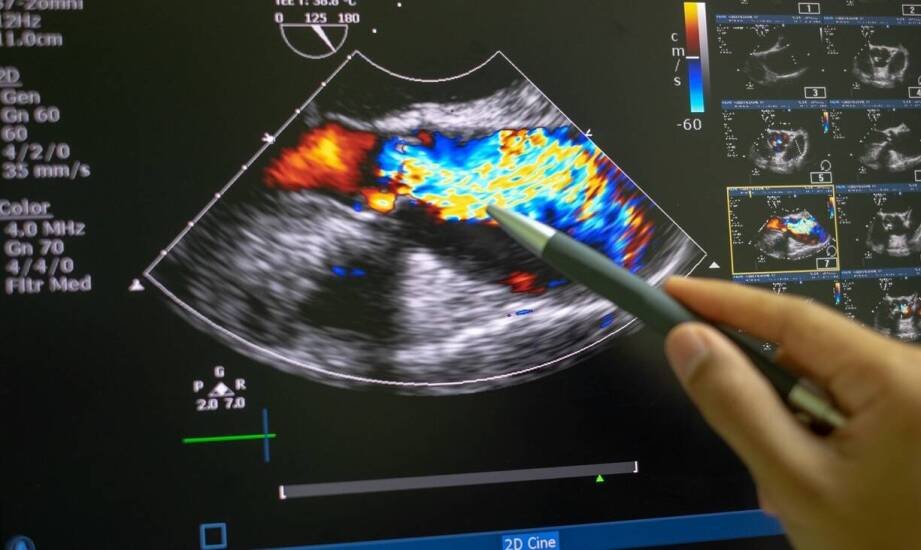

Ultrasonografia 3D i 4D ma na celu wielopłaszczyznową ocenę budowy serca płodu, uwidaczniając komory, przedsionki, przegrodę międzykomorową i zastawki. Badania serca płodu w Lubuskiem oraz obrazy przestrzenne i sekwencje ruchu mogą być stosowane do analizy funkcji skurczowo-rozkurczowej, oceny kierunku i natężenia przepływów oraz oceny nieprawidłowości anatomicznych. Na podstawie pomiarów możliwe jest określenie wymiarów jam serca, stosunku struktur oraz obecności przecieków śródsercowych. Rejestracja wideo może służyć konsultacjom z kardiologiem prenatalnym oraz planowaniu dalszej diagnostyki, w tym ewentualnego skierowania na dalsze badania lub przygotowania do opieki okołoporodowej.

Echokardiografia płodu to badanie ultrasonograficzne, które koncentruje się na ocenie struktury i funkcji serca prenatalnego. W połączeniu z obrazowaniem 3D/4D umożliwia ocenę dynamicznych aspektów pracy serca, takich jak ruch zastawek, kurczliwość ścian oraz przepływy w dużych naczyniach. Badanie obejmuje szczegółową ocenę czterech jam serca, przegród, wielkości zastawek, outflow traktu oraz relacji przestrzennych struktur. Dzięki dopplerowskim pomiarom określa się kierunek i prędkość przepływu, co służy ocenie przecieków, zwężeń czy niedomóg zastawek. Echokardiografia wspomaga planowanie dalszej diagnostyki, wskazując potrzebę konsultacji kardiologicznej oraz dodatkowych badań prenatalnych w Lubuskiem lub w innych regionach. Umożliwia również ocenę obrazu wrodzonych wad serca oraz stanu płodu w odniesieniu do planowanej opieki do- lub po‑porodowej, co może ułatwić przygotowanie zespołu medycznego oraz rodziny na opiekę nad noworodkiem.